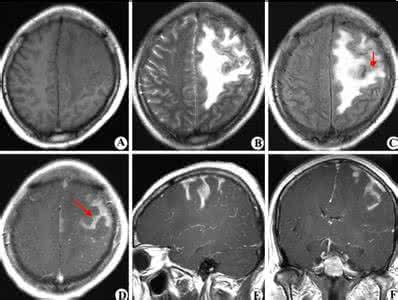

【功能主治】清热解毒,镇惊开窍。用于热病高热烦躁,神昏谵语;中风昏迷及脑炎、脑膜炎,中毒性脑病,脑出血,败血症等具有上述症状者。